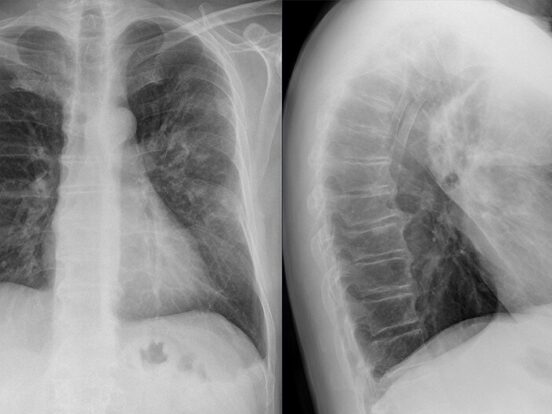

A severe type of pneumonia caused by Legionella bacteria—most often Legionella pneumophila—Legionnaires’ disease typically develops 2 to 10 days after exposure. In rare cases, this can extend to 14 days or more.Wikipedia+15Wikipedia+15Houston Chronicle+15

Symptoms may resemble flu or pneumonia and typically include cough, high fever, muscle aches, headache, and shortness of breath. Additional signs—such as nausea, confusion, or diarrhea—are also possible.CDC

4. Diagnosis & Treatment Options

Diagnosis often involves the urinary antigen test or sputum cultures. Effective antibiotics include macrolides (like azithromycin) and quinolones (like levofloxacin), with treatment durations typically ranging from 3–10 days depending on the agent and severity.Wikipedia+1